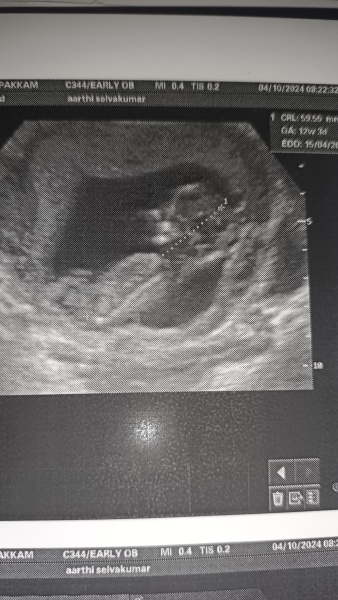

aarthishinzu · 05/10/2024 11:08

Any ideas on finding the sex of my baby. 12weeks and 3days old scan. 😅